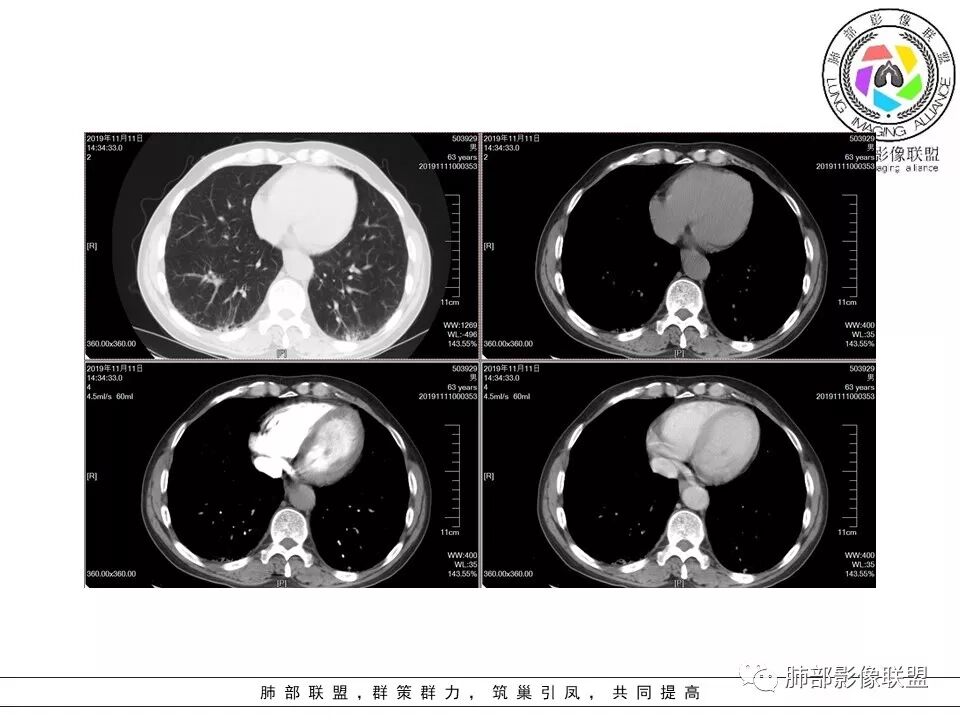

南边:糊墙,长轴与胸膜平行;边缘收缩+膨隆;脐凹征

常规:隐球菌与癌鉴别

脐凹征,高度提示恶性

因为其与胸膜的关系与右上叶的不一致,所以不能一元论

而且周围的表现不一致

还有就是间质性病变基础上,恶性变的几率很高